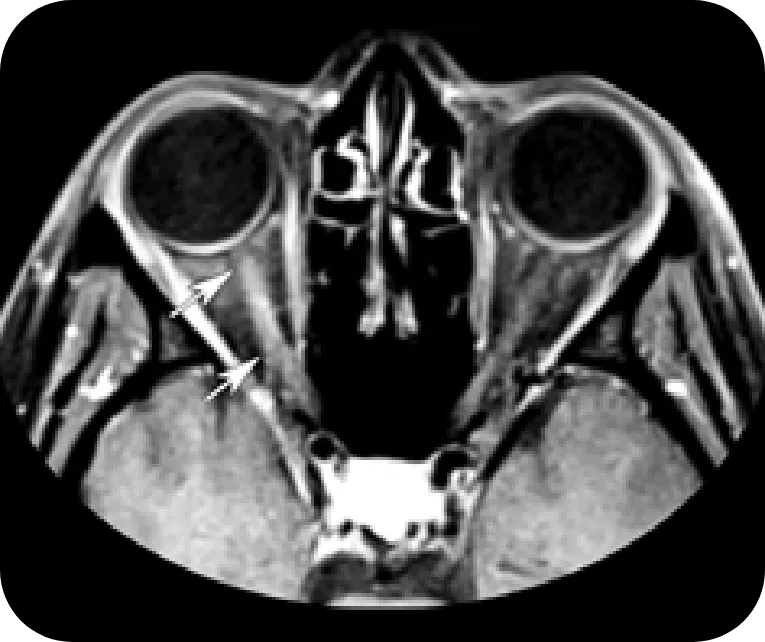

Optic Nerve

NMOSD

Extensive bilateral gadolinium-enhancing lesions at the posterior portion of the optic nerves (arrows)

Reprinted with permission from Radiographics, 2018;38(1):169-193. ©RSNA

MS

Unilateral and short-length involvement of the right intraorbital optic nerve (arrows) showing the typical pattern of MS